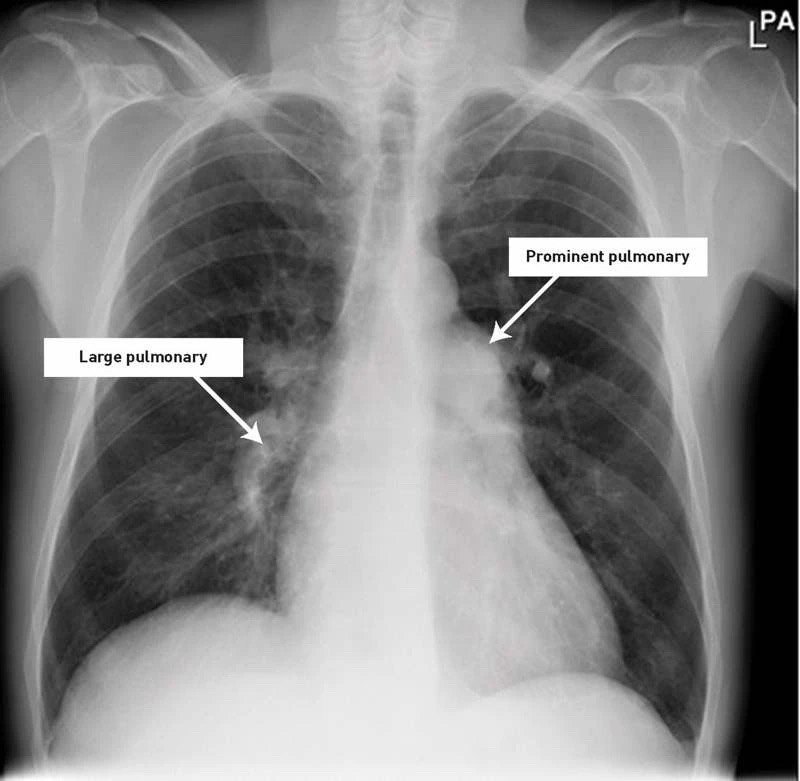

先天性心臟病已經(jīng)成為我國(guó)首位出生缺陷疾病。毫無疑問,外科是先天性心臟病首選的治療方案。最近十年內(nèi),我國(guó)先心病外科水平有了長(zhǎng)足的進(jìn)步,一些高難度的手術(shù)得到普及并在此基礎(chǔ)上有所創(chuàng)新,而一些常見先天性心臟病治療的成功率已經(jīng)達(dá)到西方發(fā)達(dá)國(guó)家的水平。不容忽視的是先心病合并肺動(dòng)脈高壓仍然是我國(guó)先心病外科面臨的巨大挑戰(zhàn)。 對(duì)于合并器質(zhì)性肺高壓(即艾森曼格綜合癥)患兒禁忌施行心臟畸形治療,已經(jīng)成為共識(shí)。隨著先心病外科的普及以及國(guó)家醫(yī)保制度的完善,現(xiàn)在此類患者的比例已經(jīng)日趨減少。而隨著近年來針對(duì)肺動(dòng)脈高壓靶向治療藥物的應(yīng)用,更使一些處于邊緣狀態(tài)的重度肺動(dòng)脈患者獲得了手術(shù)機(jī)會(huì)。先心病術(shù)后肺動(dòng)脈高壓仍是目前我國(guó)先心病外科一個(gè)需警惕的盲區(qū)。 術(shù)后早期住院期間PAH由于在嚴(yán)密的監(jiān)控下,通過呼吸機(jī)管理,一氧化氮吸入等處理,其PAH危象往往能得到控制。二師兄更多關(guān)注是患者出院后的持續(xù)性PAH,而且此類患者比例并不低。我國(guó)室間隔缺損合并重度PAH患者的術(shù)后隨訪中,其術(shù)后10年生存率為90%,術(shù)后18年的預(yù)期生存率僅為62%~67%。所有這些合并重度PAH患者術(shù)后幾乎均未接受控制肺動(dòng)脈高壓的治療,其中僅3%患者接受了降低PAH的藥物治療,僅6%患者接受了抗凝治療??梢娦g(shù)后PAH存在很大的潛在危害性,因?yàn)槠渫鶠榧覍俸歪t(yī)師所忽視。 造成術(shù)后長(zhǎng)期持續(xù)性肺動(dòng)脈高壓的主要原因包括二點(diǎn),其一是術(shù)前多肺血患者大量左向右分流造成肺血管床阻力增高,如前述的合并重度肺動(dòng)脈的室間隔缺損。雖然術(shù)后心內(nèi)分流被阻斷,但PAH導(dǎo)致的肺血管床的惡性重構(gòu)需要較長(zhǎng)的一段時(shí)間去恢復(fù),甚至個(gè)別患者血管病變無法逆轉(zhuǎn)。其二就是術(shù)前少肺血的紫紺先心病患者。由于長(zhǎng)期缺乏正常的肺血流的灌注,其肺血管床往往發(fā)育不良。如肺動(dòng)脈閉鎖患者雖然兩側(cè)固有肺動(dòng)脈的發(fā)育可以夠根治術(shù)的標(biāo)準(zhǔn),但肺內(nèi)出現(xiàn)葉段的動(dòng)脈缺失,所以根治術(shù)后發(fā)育欠佳的肺血管床難以容納突然增加的肺血流,從而PAH持續(xù)偏高,導(dǎo)致右室壓力很高甚至需被迫將室間隔缺損的補(bǔ)片拆除或開窗。 先天性心臟病術(shù)后肺動(dòng)脈高壓是一個(gè)值得警惕的盲區(qū),需要我們從整體上對(duì)其進(jìn)行綜合處理。首先要樹立PAH的“Treat-Repair-Treat”的概念,即不僅僅要在術(shù)前積極降壓,而且術(shù)后也要密切隨訪,要和患者家屬充分溝通,積極藥物治療。其次,要制訂個(gè)體化的手術(shù)方案,不強(qiáng)求完美,而是通過肺動(dòng)脈環(huán)縮術(shù)、室間隔缺損補(bǔ)片開窗等手段,來使患者術(shù)后的肺血流達(dá)到理想的平衡,從而提高遠(yuǎn)期存活率。 所以,有時(shí)候我會(huì)讓一些孩子吃藥多吃久一些,3~6個(gè)月的時(shí)間,強(qiáng)心利尿補(bǔ)鉀+西地那非+波生坦治療。就是擔(dān)心一些孩子術(shù)后沒有規(guī)律性服藥,出現(xiàn)這種情況。見過幾個(gè)成人,重度肺動(dòng)脈高壓,室缺做完,早期認(rèn)為做完手術(shù)就沒事,但是沒多久復(fù)查就是重度肺動(dòng)脈高壓。照片中的大孩子就是室缺肺動(dòng)脈高壓術(shù)后。長(zhǎng)期服用強(qiáng)心利尿+波生坦治療。去年,孩子青春期,可能某些原因,自己停藥,很快就感覺不舒服。孩子爸爸馬上帶他來醫(yī)院讓我看看。追問病史,孩子自己把藥停了。我叮囑孩子和孩子爸爸,回去一定把藥吃上。吃上以后,沒多久就好了很多。 生活方式的改變也可以幫助改善狀況。可考慮以下這些建議: 充分休息。休息可以減少由肺動(dòng)脈高壓引起的疲勞。 盡可能保持適當(dāng)?shù)幕顒?dòng)。對(duì)于一些患有肺動(dòng)脈高壓的人來說,即使是最溫和的運(yùn)動(dòng)形式也可能太過勞累。對(duì)另一些人來說,適度的運(yùn)動(dòng)如散步可能是有益的——尤其是在有氧治療期間。但要依據(jù)專業(yè)醫(yī)生的建議。 在大多數(shù)情況下,建議患有肺動(dòng)脈高壓的人不要舉重物。專業(yè)醫(yī)生可以幫助病人設(shè)計(jì)適當(dāng)?shù)腻憻捰?jì)劃。 戒煙。對(duì)于吸煙的人而言,最重要的事情就是戒煙,同時(shí)還要避免二手煙。 避免懷孕和避孕藥。避孕藥會(huì)增加血栓的風(fēng)險(xiǎn)。肺動(dòng)脈高壓會(huì)給媽媽和寶寶帶來嚴(yán)重的并發(fā)癥。 不要去高海拔地區(qū)旅行或居住。高海拔會(huì)加重肺動(dòng)脈高壓的癥狀。 避免出現(xiàn)血壓過低的情況。這些包括坐在熱水浴缸或桑拿浴或長(zhǎng)時(shí)間洗熱水澡或淋浴。這些會(huì)降低血壓,導(dǎo)致昏厥甚至死亡。也要避免那些導(dǎo)致長(zhǎng)時(shí)間緊張的活動(dòng),比如舉起重物。 健康飲食,控制體重。以健康飲食為目標(biāo),包括全谷類、水果和蔬菜、瘦肉和低脂奶制品。避免飽和脂肪、反式脂肪和膽固醇。必要時(shí)要限制飲食中的鹽含量。保持健康的體重。